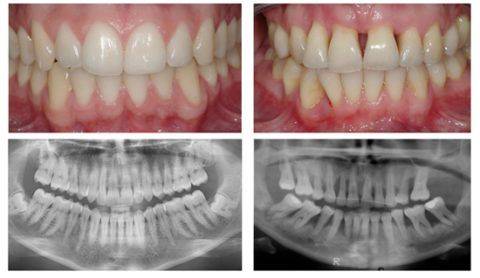

Речь идет о достижении пациентом ремиссии и поддержании состояния ремиссии. После достижения ремиссии лечебные мероприятия под названием “лечение пародонтита” направлены на восстановление утраченных тканей пародонта и зубов путем пародонтологической хирургии, имплантации и эстетического протезирования зубов коронками и винирами, несъемными мостами и съемными протезами, см. на фото:

Катаральное воспаление десен

Патологический карман

Рентгенологический снимок – резорбция челюсти

Атрофическое воспаление десен

Оголение передней группы зубов

Резорбция челюсти